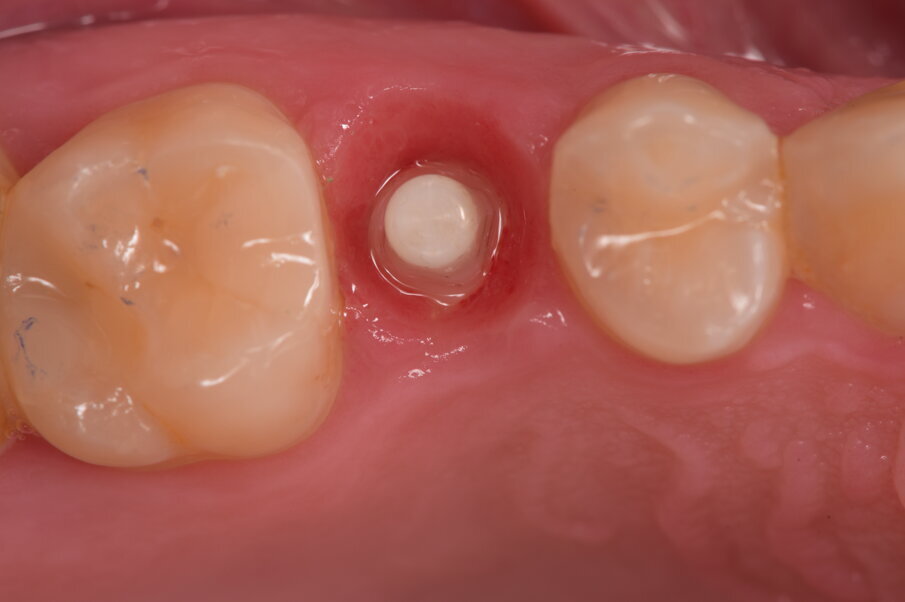

Il flusso di lavoro digitale non prevede uno specifico scan body pertanto l’impronta si deve rilevare come per un elemento naturale. Nello specifico però la profondità del tunnel gengivale perimplantare (Fig. 7) non consente una precisa lettura dell’intero perimetro del collarino implantare pur con l’utilizzo di fili retrattori, pertanto abbiamo optato per un’impronta convenzionale con lo specifico utilizzo del transfer a strappo, il cui colore contraddistingue la lunghezza del moncone implantare (Fig. 8).

Fig. 7_Dopo 3 mesi siamo soliti eseguire un controllo radiografico e di conseguenza si rimuove il provvisorio e rivalutando il contorno mucogengivale perimplantare, in caso di necessita si interviene nella modifica del provvisorio.